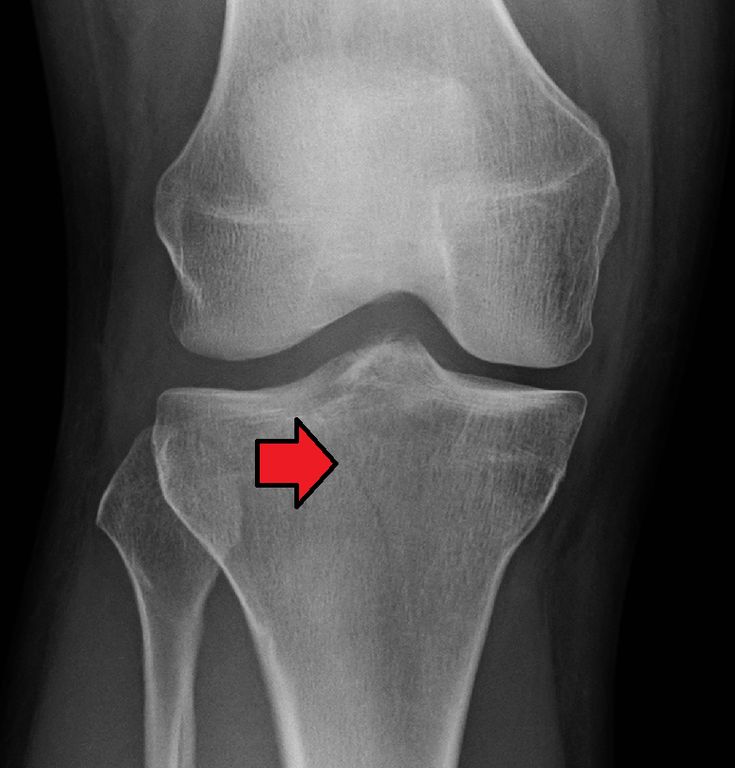

Diagnosis of Complex Fractures

Understanding how the injury happened

Checking pain, swelling, and movement

X-rays to identify the Bone fracture

CT scan or MRI for complex injuries

How do you diagnose complex fractures?

We use digital X-rays, CT scans, MRI scans, and 3D imaging to accurately evaluate fracture patterns and surrounding tissue damage.